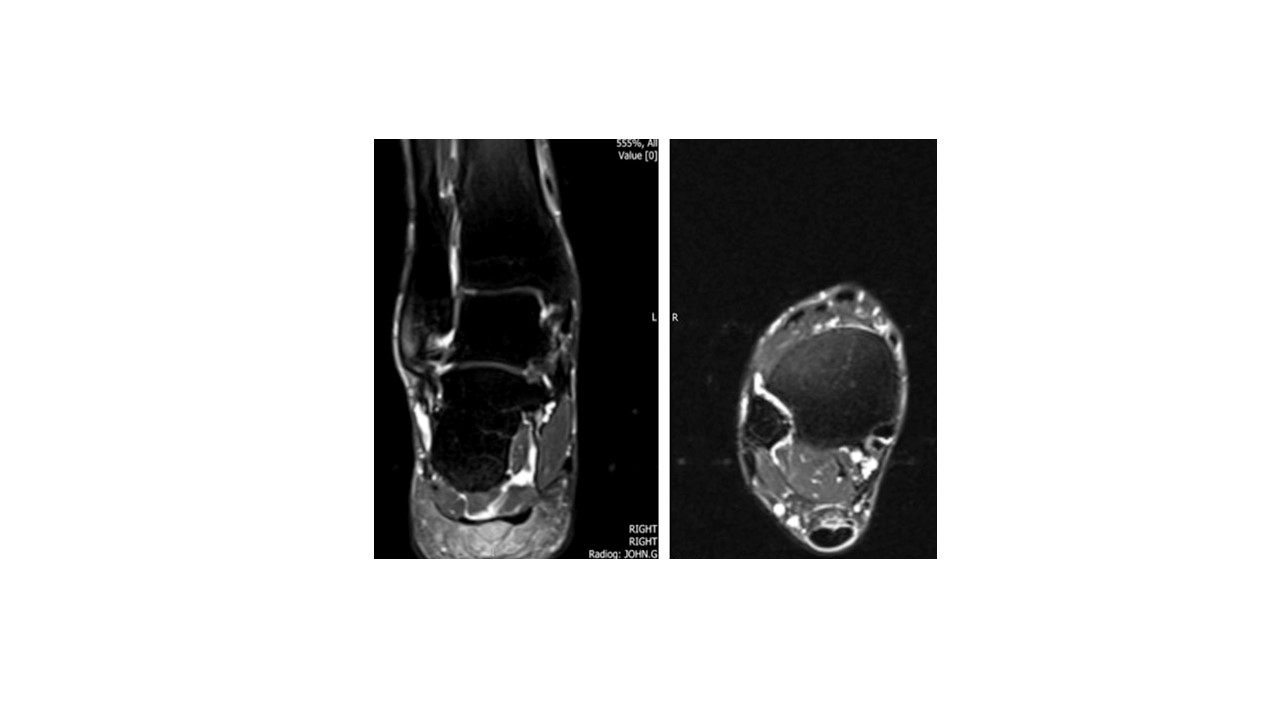

MRI- fluid-weighted sequence showing coronal (frontal) and axial (transverse) slices through the ankle joint at the level of ankle syndesmosis where the front, intermediate and posterior syndesmotic ligaments are torn- demonstrated by the tracking ankle effusion.